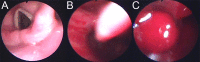

Figures